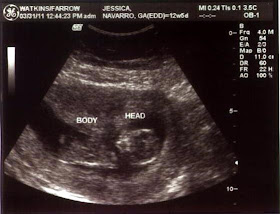

2/24/2011: I didn't bleed anymore all night, but I feel off and on cramping and a mildly painful pressure at my va-j-j. Of course I don't know if that is just normal uterus cramping or miscarriage cramping. I also don't seem to be nauseous this morning, although I took my pills on an empty stomach and within about 10 minutes I was hurling everything back up. Of course this could be nerves from my pending OB appointment today. Our original appointment was 1:30pm, but the stenographer was not going to be there so they rescheduled us for 10:20am. We went in for the sonogram first. I could instantly tell that she was having problems locating anything. I finally asked her if it was "a fake pregnancy". "Is there nothing there?" I asked. She said that I have an enlarged uterus and she was having some difficulty locating the fetus within the sac. Then she said it appeared I had fibroids and that was causing additional difficulty in what she could see. My heart sank and she continued to pillage my uterus. Suddenly there were two sacs! Apparently it was twins!!! One had not properly formed and was not viable, but the second appeared to be ok. She began to take measurements and told us it was tracking at 7 weeks 5 days. We also saw the heart beat! It was just a little flicker, but it looked strong. It was beating 142 beats per minute, which was great. They think the bleeding yesterday was possibly from the first non-viable fetus or possibly just natural spotting; there is really no way to know for sure; but the rest of the exam went very well and everything seems to be progressing normally! The doctor said the second fetus would probably just absorb the first and had we not had the sonogram today, we would have never known about the twin. I didn't even realize twins ran in my family. My grandmother's - father's - mother had twins. Apparently my grandma's cousin also had twins and they are the most recent set. My first OB appointment I weighed 222.2.....I really wanted to ask to take off all my clothes. LOL! The doctor said I needed to spend the next couple of days with my feet up relaxing and then I needed to not be strenuous after that; basically go to work and then go home and lay down. I cancelled my scrapbook retreat for this weekend. I just don't want to risk anything. We were in shock yet again. We prepared ourselves for the worst and never dreamed we would get such wonderful news. I prayed to God for a miracle and the last 24 hours has been pretty rough. God answered our prayers!

3/31/2011: Today was our 2nd official Dr. visit. Today was the "genetic testing". They did a sonogram, this one was exterior on my tummy....wow the baby has grown that much? At almost 13 weeks, I assumed this one would still be vaginal. The baby definitely has Juan's A.D.D. LOL, the baby was constantly rolling and the tech had a bit of a problem getting the baby in the right position. They check for a few things when the do the genetic testing. First they measured the distance of the head to neck, although I don't know how she could tell which was the neck. If it is 3 cm or less, that is a good indicator and our little peep was at 1 cm. They also check for a nasal bone, which our little alien had.....pause on alien. The tech gave us a photo of the profile, which I could totally see and one of the face....which totally looks like an alien! The eyes are like stips vertical and nothing like a baby. So from this point forward, I'm referring to our baby as the little alien. Back to the testing, they also took 5 drops of blood from my finger. The blood test tells them what is the percent likelihood that the baby could have genetic issues; but we won't find out those results for 10 days! Also, based on the last ultrasound the baby should be at 12 weeks, 5 days and the baby today measured 12 weeks, 4 days. The doctor said that she wasn't concerned about the one day difference at all and that everything was green lights and positive. The heartbeat on the sonogram was at 165 beats per minute, although we still couldn't hear it on the doppler externally. The doctor said she wasn't worried as the sonogram is a better test than the doppler and it was probably just a little too soon and we would try again next appointment. My weigh in was 223.6, only 1.5 lbs up from the appointment a month ago and I ate lunch right before my appointment so that is also good. Doc also said it was ok to stop taking the progesterone! It's just crazy thinking there is a baby inside me growing.

The sonographer first confirmed our baby's gestational age by measuring him from crown to rump to see if he's about the size he should be for his age. Our little alien was tracking right on schedule at 12 weeks, 4 days. Based on our last sonogram it should be at 12 weeks, 5 days; but the OB was not worried about a single day discrepancy. Then the tech positions the sensor, called the transducer, over my abdomen so that our baby's nuchal fold area shows up on the monitor and measures the thickness of it on the screen with calipers.Our OB was looking for 3cm or less measurement and our baby was 1cm!

Another item they look for is whether or not there is a nasal bone present. A nasal bone is a good indicator that all is well. Our little one looked like an alien, but did have a nasal bone!

5/16/2011 - We had our level II sonogram for "advanced maternal age" today. We also found out it's a GIRL! She is 10oz and everything is perfect. She is in the 30th percentile and the doctor indicated that anything over the 10th percentile is normal. During the sonogram, Juan said, "Is that a vagina?" the doctor sort of skirted his question and then a few minutes later said, "Yes, daddy, it is a girl." Right after that I looked over at Juan to see him frantically texting on his phone. He literally missed the rest of the sonogram because he was too busy spreading the word. After the appointment, he said, "She did have two arms and two legs, right?" I replied, "Yes, and two ears." He replied, "She didn't show us her ears." Too which I responded, "Yes she did, you were just too busy texting to pay attention!!!" Needless to say, he is very excited. I was too. After we left, I couldn't stop bawling. I was just so happy that everything was ok. After all the packing and straining over the past week and a half, I was really worried that something would be wrong. I also don't think I really thought it was going to happen until they told us it was a girl. Now it sort of seems real. As we were driving around after the appointment, Juan says, "Oh my gosh, our baby is part mexican, part white....she's a little coconut! We should call her Coco!" We are NOT naming our baby Coco, but that has quickly become her nickname.

8/15/2011 Today was our follow up Maternal Fetal medicine sonogram for my "advanced" maternal age with Dr. Koster. Everything is tracking beautifully with Madalynne! Her head is sized at exactly 32 weeks, her limbs are tracking at exactly 32 weeks and her belly is tracking at 33 weeks. There is plenty of fluid around her and she has already turned head down preparing for her entrance into the world. She is perfectly average, which is something I never thought I would love to hear! She is measuring 4-1/2 lbs, again perfectly on track. We began discussing the concern with preclampsia as my mother and sister both had it. She said that early indicators for preclampsia is actually a small belly. Apparently preclampsia doesn't allow enough nutrients to get to the baby. The baby takes what she can, which goes directly to her brain and extremities, not leaving enough for her tummy and essentially forcing a baby diet. With preclampsia, the baby's tummy is actually undersized, so the fact that Madalynne's belly is tracking a week larger is actually good. She is healthy.